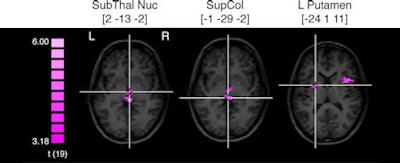

![]() |

| Axial images of seven brain regions with crosshairs indicating center of mass and brain activity when switching or repeating tasks. Images courtesy of the Proceedings of the National Academy of Sciences and the University of New Hampshire. |